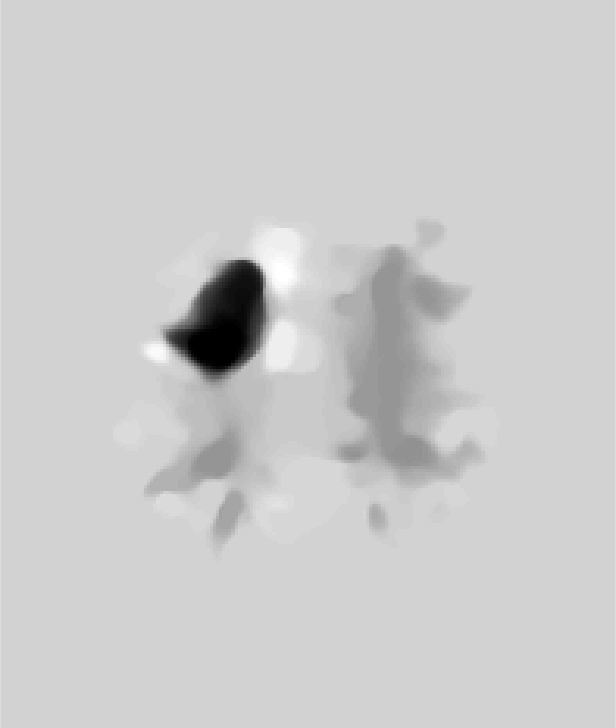

Fig. 9 (left) visualizes the average brain mask errors for IBSR and LPBA40. All images are first affinely registered to the atlas. Then we transform the gold-standard expert segmentations as well as the automatically obtained brain masks of the different methods to atlas space. We compare the segmentations by counting the average over- and under-segmentation errors over all cases at each voxel. This results in a visualization for areas of likely mis-segmentation. Our PCA model, ROBEX, BEaST (BEaST*) and BET perform well on these two datasets. Compareed to our model, ROBEX, BEaST (BEaST*) and BET show larger localized errors, e.g., at the boundary of the parietal lobe, the occipital lobe and the cerebellum. While MASS, BSE and CNN perform well on the LPBA40 dataset, they perform poorly on the IBSR dataset. This is in particular the case for the CNN approach.

Finally, Fig. 9 (right) shows the average segmentation errors on the BRATS and TBI datasets: our PCA method shows fewer errors than most other methods in these two abnormal datasets. MASS also shows few errors, while ROBEX, BEaST (BEaST*) and BET exhibit slightly larger errors at the boundary of the brain. CNN and BSE particularly show large errors for the BRATS dataset presumably again due to the coarse resolution of the BRATS data.

Figure 9: Examples of 3D volumes of average errors for the normal IBSR and LPBA40 datasets, as well as for the pathological BRATS and TBI datasets. For IBSR/BRATS, we show results for BEaST*. Images and their brain masks are first affinely aligned to the atlas. At each location we then calculate the proportion of segmentation errors among all the segmented cases of a dataset (both over- and under-segmentation errors). Lower values are better (a value of 0 indicates perfect results over all images) and higher values indicate poorer performance (a value of 1 indicates failure on all cases). Clearly, BSE and CNN struggle with the BRATS dataset whereas our PCA method shows good performance across all datasets.